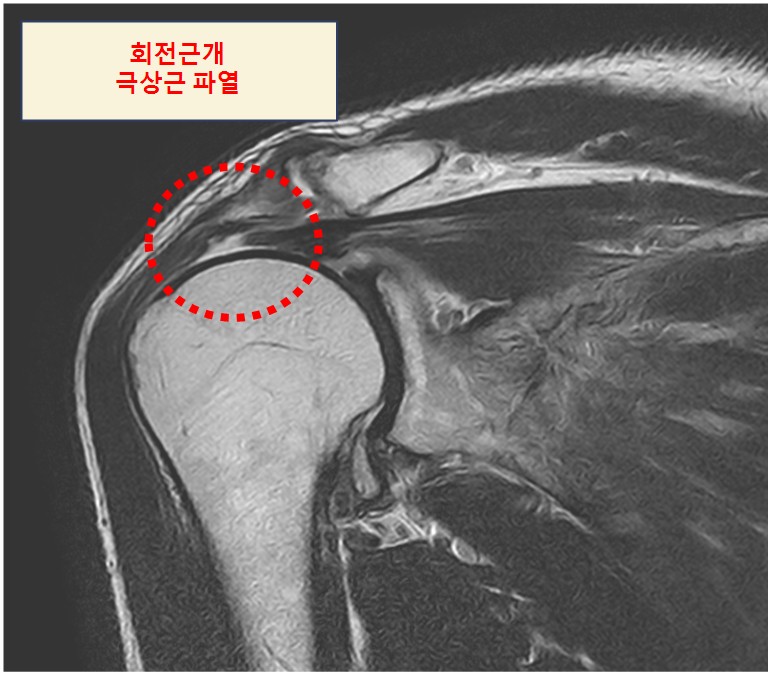

회전근개 근육(Rotator cuff muscles)은 팔을 움직일 때 어깨에 안정성을 제공해 주는 극상근(Supraspinatus muscle), 견갑하근(Subscapularis muscle), 극하근(Infraspinatus muscle), 소원근(Teres minor muscle)을 말하며 각 앞글자를 따서 'SIT muscles'이라고도 합니다.

이 근육들은 팔을 올릴때 어깨뼈와 근육 사이 찝힘이 나타나면서 근육이나 힘줄에 구멍이 생기고 부분파열이 점차 커지는 상황을 회전근개 파열이라고 말하고 있으며 주로 팔을 올릴 때 작용하는 극상근(Supraspinatus muscle)의 찢김에 의해 발생합니다.

오십견의 경우 팔을 올릴 때 끝부분에서 통증이 있다면 회전근개 파열은 수동적으로는 팔을 끝범위까지 올릴 수 있지만 스스로 근육의 힘으로 팔을 올릴 경우 중간 범위부터 통증이 발생합니다.

물리치료, 운동 등으로 호전이 되지 않는 경우 MRI 등 정밀 검사를 통해 얼마나 손상이 있는지 확인하고 수술적인 방법을 고려해 볼 수 있습니다.

보통 파열의 길이를 기준으로 극상근 파열이 3cm 이하이면 보존적 치료, 3cm 이상이면 수술적 치료를 고려해야 합니다.